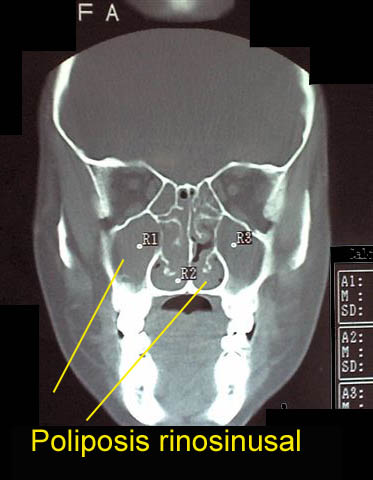

Causas de obstrucción nasal

Pueden ser causa de obstrucción nasal: rinitis viral, bacteriana o alérgica; sinusitis aguda, sinusitis crónica; agentes irritantes o contaminantes; causas hormonales, medicamentos locales; enfermedades autoinmunes; pólipos inflamatorios: poliposis rinosinusal, poliposis nasal recidivante; engrosamiento crónico de cornetes; desarrollo de adenoides; causas tumorales; alteraciones de la anatomía nasal por traumatismos o por trastornos durante el desarrollo; cornetes bullosos (muy desarrollados con aire en su interior); y otras causas.